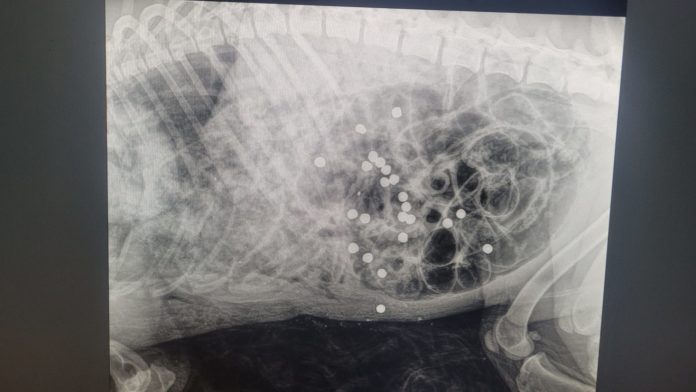

Il corpo dell’animale è stato affidato all’Istituto Zooprofilattico di Latina per l’autopsia, utile a chiarire quanto accaduto e raccogliere elementi per risalire all’autore del gesto.